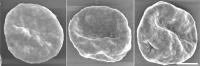

image: Giemza staining of Plasmodium falciparum the parasite that causes the most severe form of malaria. view more

Credit: Kentaro Kato, Tohoku University

The researchers focused on Plasmodium falciparum, the parasite that causes the most severe form of malaria. This parasite infects a host red blood cell, triggering the production of several proteins into the host cell's cytoplasm--the bulk of the cell's mechanics and the liquid in which they're held, ultimately transforming the cell's physical form. Not only does this transformation make the cells stick in place, out of the body's immune response, it also helps the parasite travel to the surface of the cell and infect others. Together, the proteins work to proliferate the parasite, leading to the propagation of the malaria parasite.